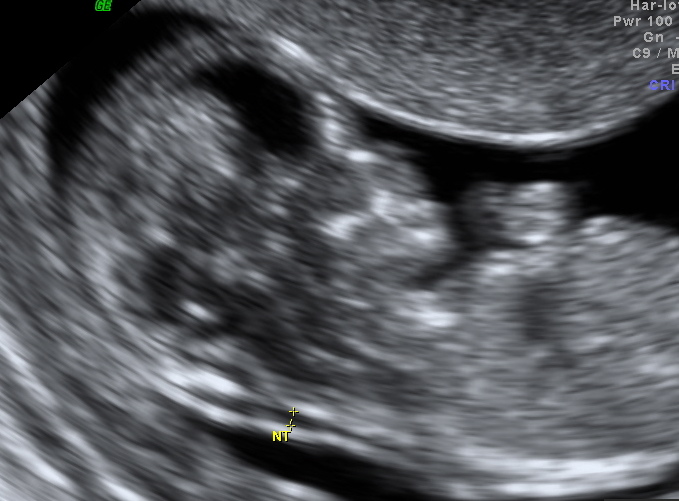

הבדיקה מבוצעת על הבטן או מהנרתיק והכל לפי החלטת הרופא. בתמונה סימנתי את השקיפות עם שתי צלבים ורשמתי NT ליד.